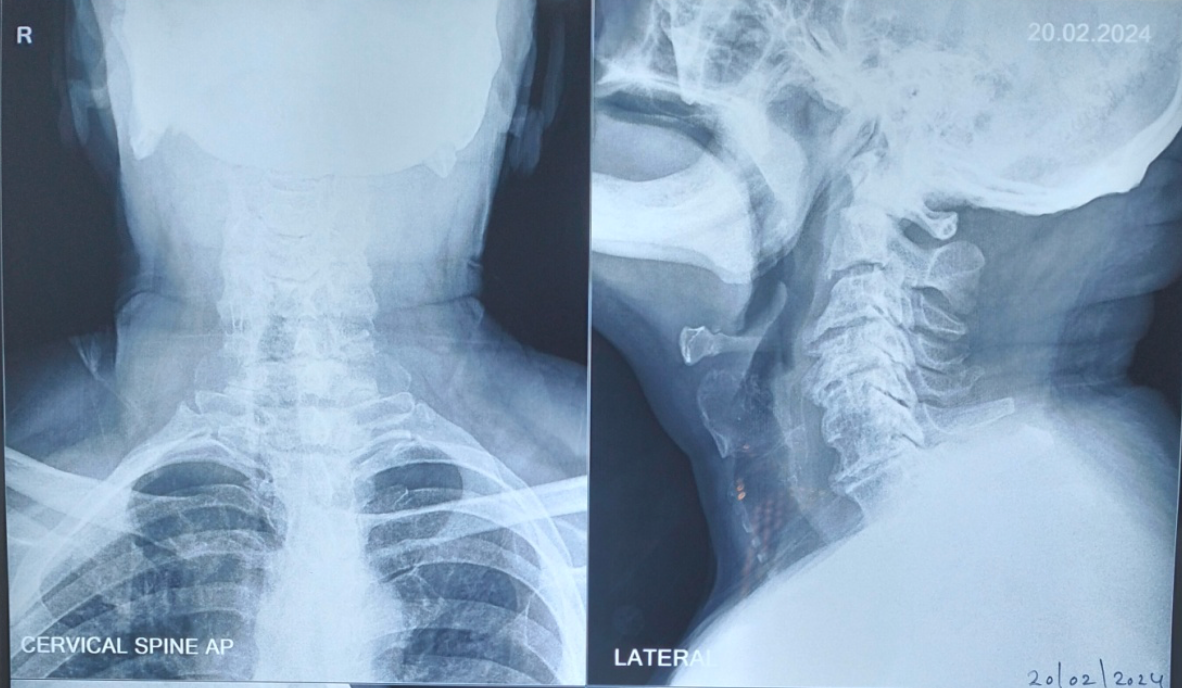

- MRI Cervical Spine: Gold standard to identify spinal cord compression and signal changes

- X-rays: To evaluate alignment, instability, and degenerative changes